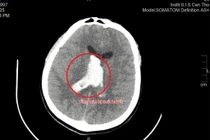

Kết quả chụp cắt lớp vi tính mạch máu (CTA) bằng siêu máy CT 1975 lát cắt cho thấy ông Năm bị tắc hoàn toàn động mạch não giữa bên trái tại vị trí nhánh M1, chiều dài khoảng 10 mm.

Bác sĩ đa chuyên khoa hội chẩn nhanh, chỉ định can thiệp nội mạch, loại bỏ cục huyết khối đang làm tắc động mạch não.